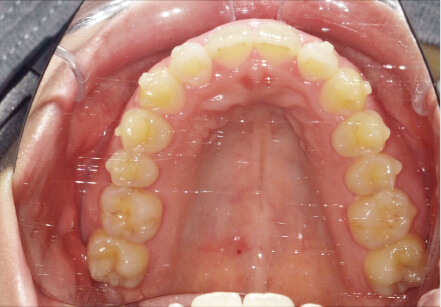

叢生の症例

19歳

女性

相談内容

上の前歯が出っ歯、下の前歯がガタガタ

カウンセリング・診断結果

抜歯承諾、IPR承諾、アタッチメント承諾、ミニインプラント承諾、アレルギー有・叢生(凸凹)

治療内容・方法

全顎アライナー矯正 抜歯予定だったが抜歯リスク高いため抜歯なしでIPR量を増やす

術後の経過・現在の様子

クリアライナー

治療のリスク

痛み・歯根吸収・歯肉退縮・虫歯・後戻り

費用・治療期間

880,000円、1年5ヶ月